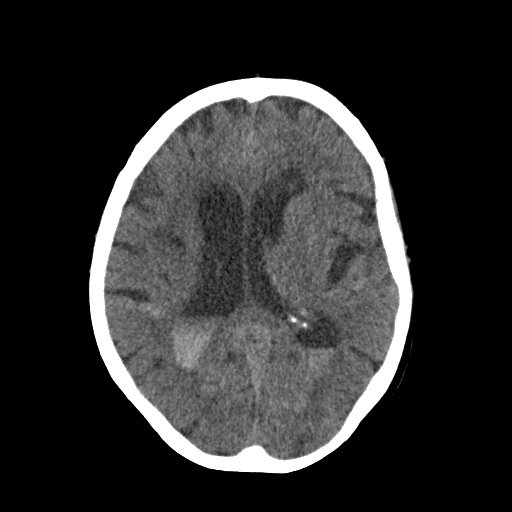

CT Scan Before Diagnosis